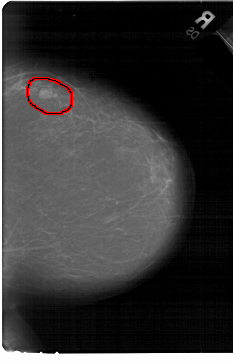

A_1440_1.LEFT_MLO

FILE: A_1440_1.RIGHT_MLO.OVERLAY

TOTAL_ABNORMALITIES 1

ABNORMALITY 1

LESION_TYPE MASS SHAPE LOBULATED MARGINS CIRCUMSCRIBED

ASSESSMENT 4

SUBTLETY 4

PATHOLOGY BENIGN

TOTAL_OUTLINES 1

BOUNDARY